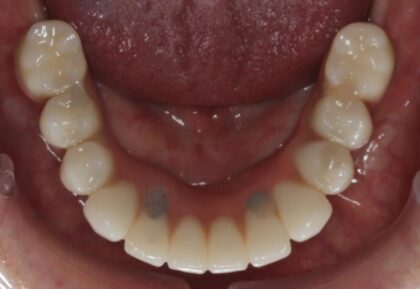

術前咬合面

術前咬合面

術後咬合面

術後咬合面

| 主訴 | 自分が一番元気に、何でも食べられる父親でいたい。家族との食事の時間が人生ですごく大切で、何とかしたい、と思っていた。 |

|---|---|

| 年代・性別 | 50代 男性 |

| 治療部位 | 上顎6~6 |

| 治療費用 |

インプラント手術料 |

| 手術回数 | 1回 |

| 治療期間 | 4ヶ月 |

| 手術時間 | 180分 |

| 治療回数 | 10回 |